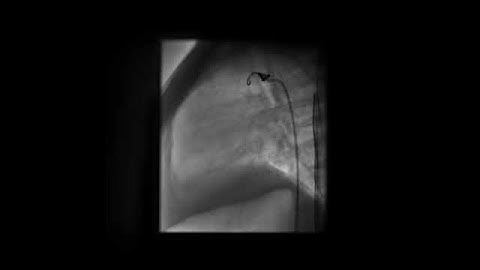

PDA coil release